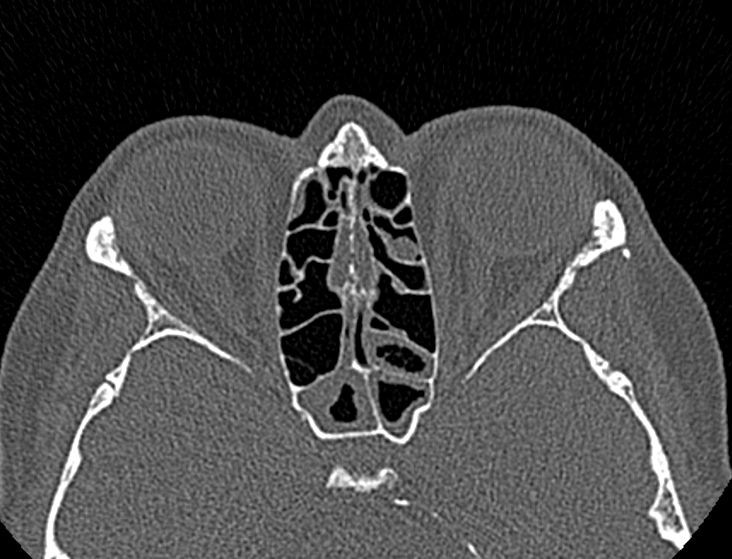

Золотым стандартом в диагностике патологических процессов пазух носа является мультиспиральная компьютерная томография, которая является быстрым безболезненным и неинвазивным (то есть без вмешательства в организм) способом исследования состояния синусов. Метод основан на проникающей способности ионизирующего излучения и получения изображений органов и тканей организма за счет разной степени поглощения ими рентгеновских лучей.

На основе полученных данных цифровые приложения томографов создают трехмерные реконструкции пазух носа, что позволяет оценить пространственное взаимоотношение анатомических структур и помогает в диагностике патологии околоносовых пазух.

Мультиспиральная компьютерная томография дает информацию о состоянии полости носа, носовой перегородки, степени воздушности околоносовых пазух, путей дренирования синусов, состоянии слезных каналов. Сканирование позволяет оценить толщину слизистой, наличие патологического содержимого в просвете пазух (уровня «жидкости»), выявить опухолевые образования. С помощью КТ можно провести точную диагностику травматических повреждений костей лицевого черепа, определить локализацию инородных тел, попавших в полости синусов.

С помощью объемной реконструкции можно перед оперативным вмешательством увидеть особенности анатомии ЛОР-органов, определить точное расположение патологического очага по отношению к окружающим тканям. Компьютерная томография помогает в диагностике аномалий развития придаточных пазух носа, слезоотводящих каналов.